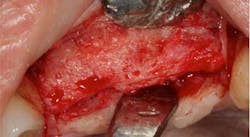

Fig. 7